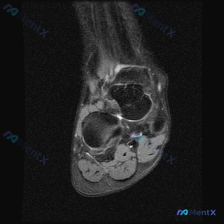

今天遇到一个有意思的读片病例,整理出来和大家分享一下,核心问题是临床怀疑软组织积液,但读片结果和初步判断完全对不上,这里把完整分析思路理一遍。 一、病例基本信息 目前核心信息是:临床怀疑足踝部存在软组织积液,提供了一张足踝部冠状位T2加权(脂肪抑制)MRI图像,要求读片判断,推测患者伴随足踝部疼痛或...